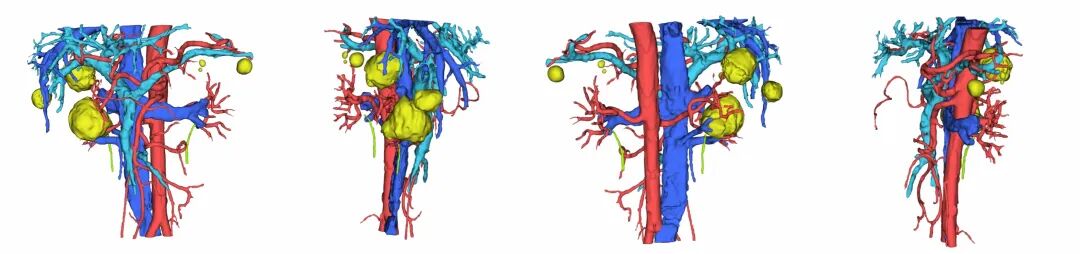

术前阿梵D——泌尿系统三维重建结果

三维重建泌尿系统动静脉预览

三维重建泌尿系统整体预览

患者肾肿瘤切除手术的难度:主要在于肿瘤生长在肾窦内,靠近肾门部,位于最复杂的肾脏核心区域,周围被肾脏动静脉及集合系统包绕,任何周围组织的损伤很有可能造成手术失败,并且肾门部背侧肾脏正常组织较少,缝合难度大,术后易出现出血、漏尿等并发症。术前运用阿梵D三维重建技术详细评估肿瘤与肾脏各分支血管的解剖关系,全方位评估手术风险。

三维重建下的肾脏及其相邻脏器